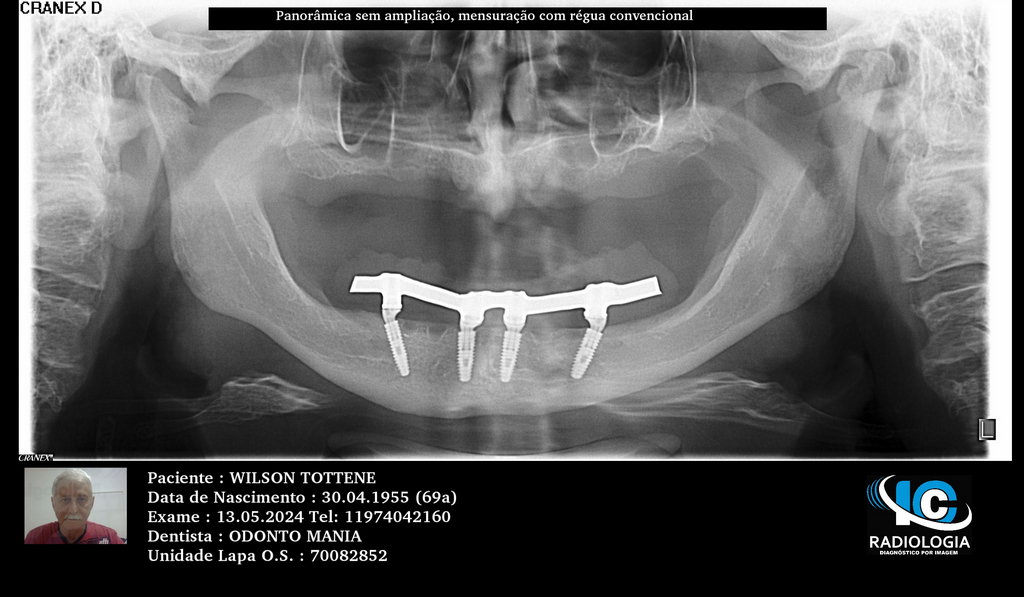

PRÓTESE TOTAL FIXA EM IMPLANTES

W.T.